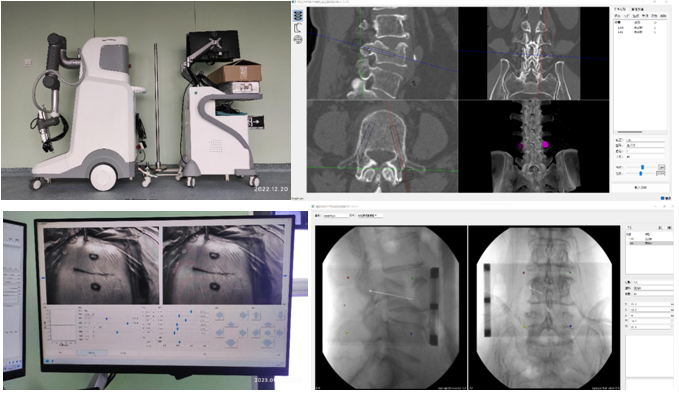

机器人辅助技术是脊柱外科手术向智能化、精准化、微创化发展的又一次飞跃。1月10日,刘时璋主任带领骨科团队精诚合作,在手术室、麻醉科及消毒供应室的鼎力协助下,成功开展黑料网首例机器人辅助局麻下“经皮球囊扩张椎体成形术(PKP)”治疗腰椎压缩性骨折。此例手术较传统的徒手穿刺更为精准、安全、高效,体现了数字医学与骨科智能化的融合发展。

患者为70岁女性,腰部疼痛伴活动受限10天,在黑料网经MRI及CT检查示:腰4椎体压缩性骨折。经专家讨论后,医疗团队拟采用机器人辅助,局麻下行经皮球囊扩张椎体成形术。经过精密的仪器调试和配准,术前进行了反复的模型演练。刘时璋主任团队将患者的CT数据与机器人系统配准,工程师团队将事先规划好的个体化穿刺路径数据植入机器人系统。将术中的正侧位X线透视数据与CT数据融合后,机械臂按照术前规划路径,一次性穿刺成功,位置精准满意。